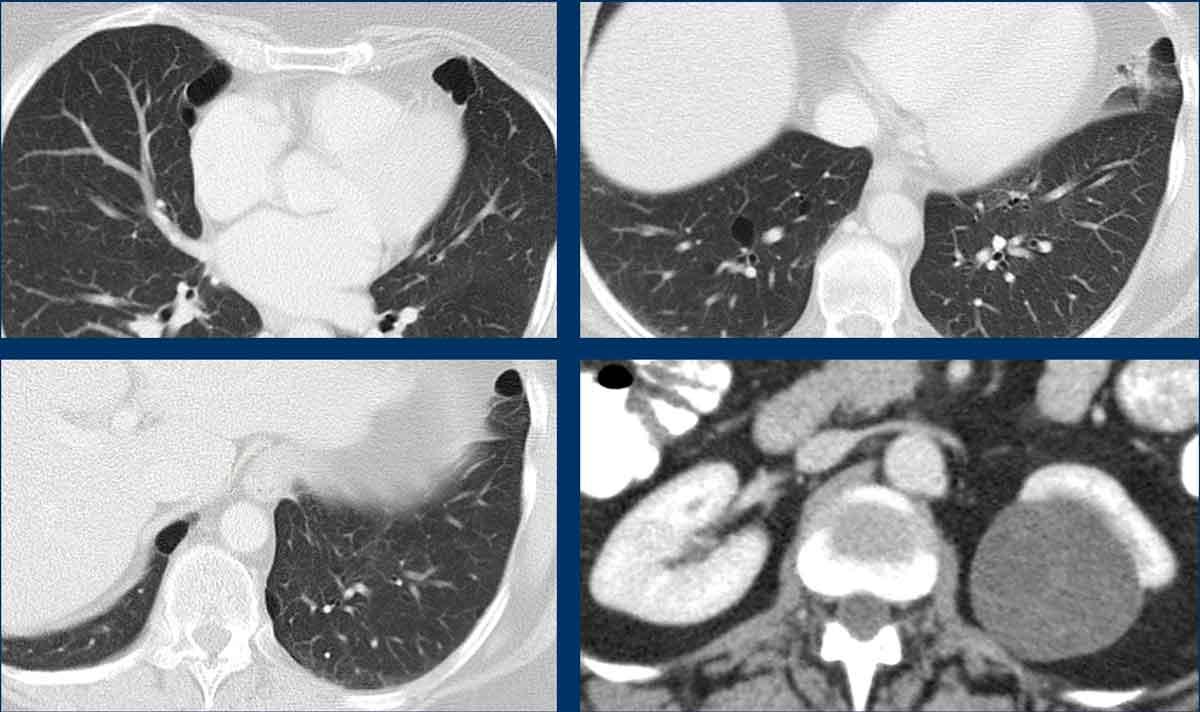

Lymphangioleiomyomatosis (LAM) là một bệnh lý tiến triển âm thầm, xảy ra đặc hiệu ở phụ nữ dưới dạng đột biến gen tản phát, trừ khi có liên quan đến phức hợp xơ cứng củ (tuberous sclerosis complex), vốn có thể là tản phát hoặc di truyền.

Bệnh nhân thường có triệu chứng khó thở, ho, đau ngực và ho ra máu.

Một số bệnh nhân biểu hiện bằng tràn khí màng phổi tự phát, tràn dịch màng phổi (tràn dưỡng chấp) hoặc có thể gặp u cơ mỡ mạch máu (angiomyolipoma).

LAM biểu hiện với số lượng lớn các nang hình tròn, bờ đều đặn, phân bố rải rác khắp nhu mô phổi.

Hình ảnh

- Nhiều nang ở một phụ nữ trẻ. Lưu ý hình dạng tròn đều và phân bố lan tỏa.

- Trường hợp LAM nặng. Khi có tiền sử hút thuốc lá, chẩn đoán phân biệt cần đặt ra là LCH (giai đoạn tiến triển).

- Tràn dịch màng phổi (dịch dưỡng chấp) ở bệnh nhân LAM.

- Phân bố lan tỏa trong LAM.

Ngoài ra, nhiều u cơ mỡ mạch máu (angiomyolipoma) được phát hiện ở vùng bụng trên.

Bệnh nhân này được xác định mắc LAM liên quan đến phức hợp xơ cứng củ (TSC – tuberous sclerosis complex).

Tỷ lệ hiện mắc u cơ mỡ mạch máu trong LAM tản phát là 40-50% và trong LAM liên quan TSC vào khoảng 80%.

Đây là trường hợp LAM nặng với nhu mô phổi bị tổn thương lan tỏa.

Nhìn chung, LAM là bệnh lý tiến triển với tiên lượng xấu.